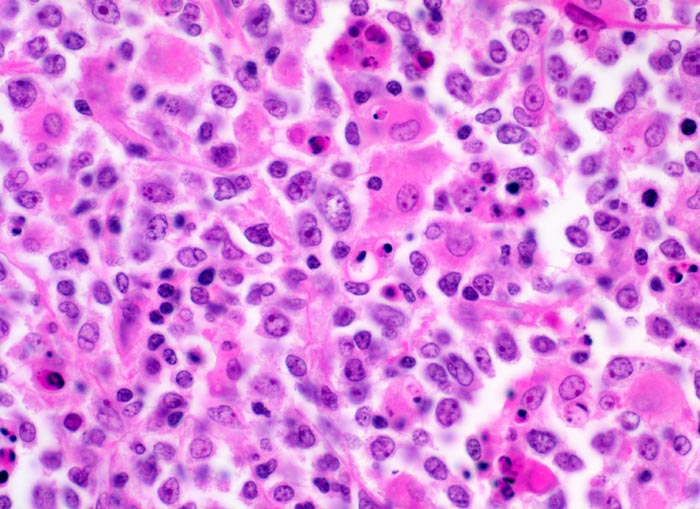

Diffuses grosszelliges B-Zell Lymphom

Mittelgrosse polymorphe Tumorzellen mit unregelmässig geformten, teils lobulierten Kernen. Gelegentlich sind mehrere randständige Nukleolen erkennbar (Zentroblastische Variante). Schmaler Zytoplasmasaum. Neben den Tumorzellen sind zahlreiche Histiozyten mit reichlich eosinophilem Zytoplasma und ovalen Kernen ohne Atypien nachweisbar. Das Zytoplasma der Histiozyten enthält teilweise phagozytierte Zelltrümmer.

Magenlymphom mit Befall abdominaler Lymphknoten.

Histologie

400